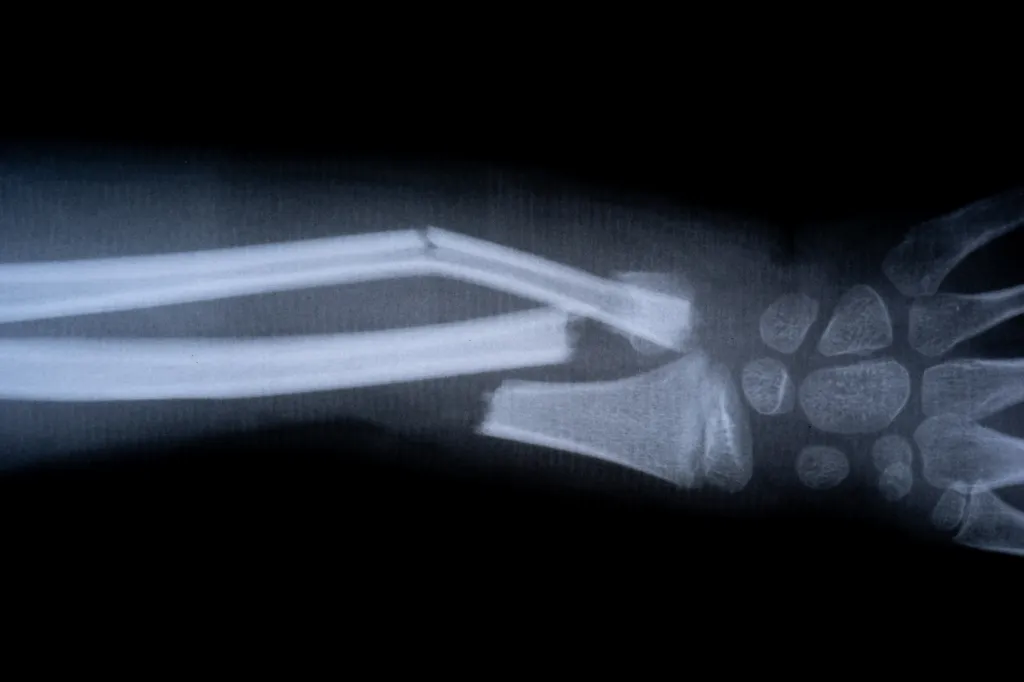

In one clinical trial, a patient with a wrist fracture was treated through a small incision. Instead of undergoing surgery with implants, the bone was repaired almost instantly. Three months later, follow-up examinations confirmed complete healing with no complications.